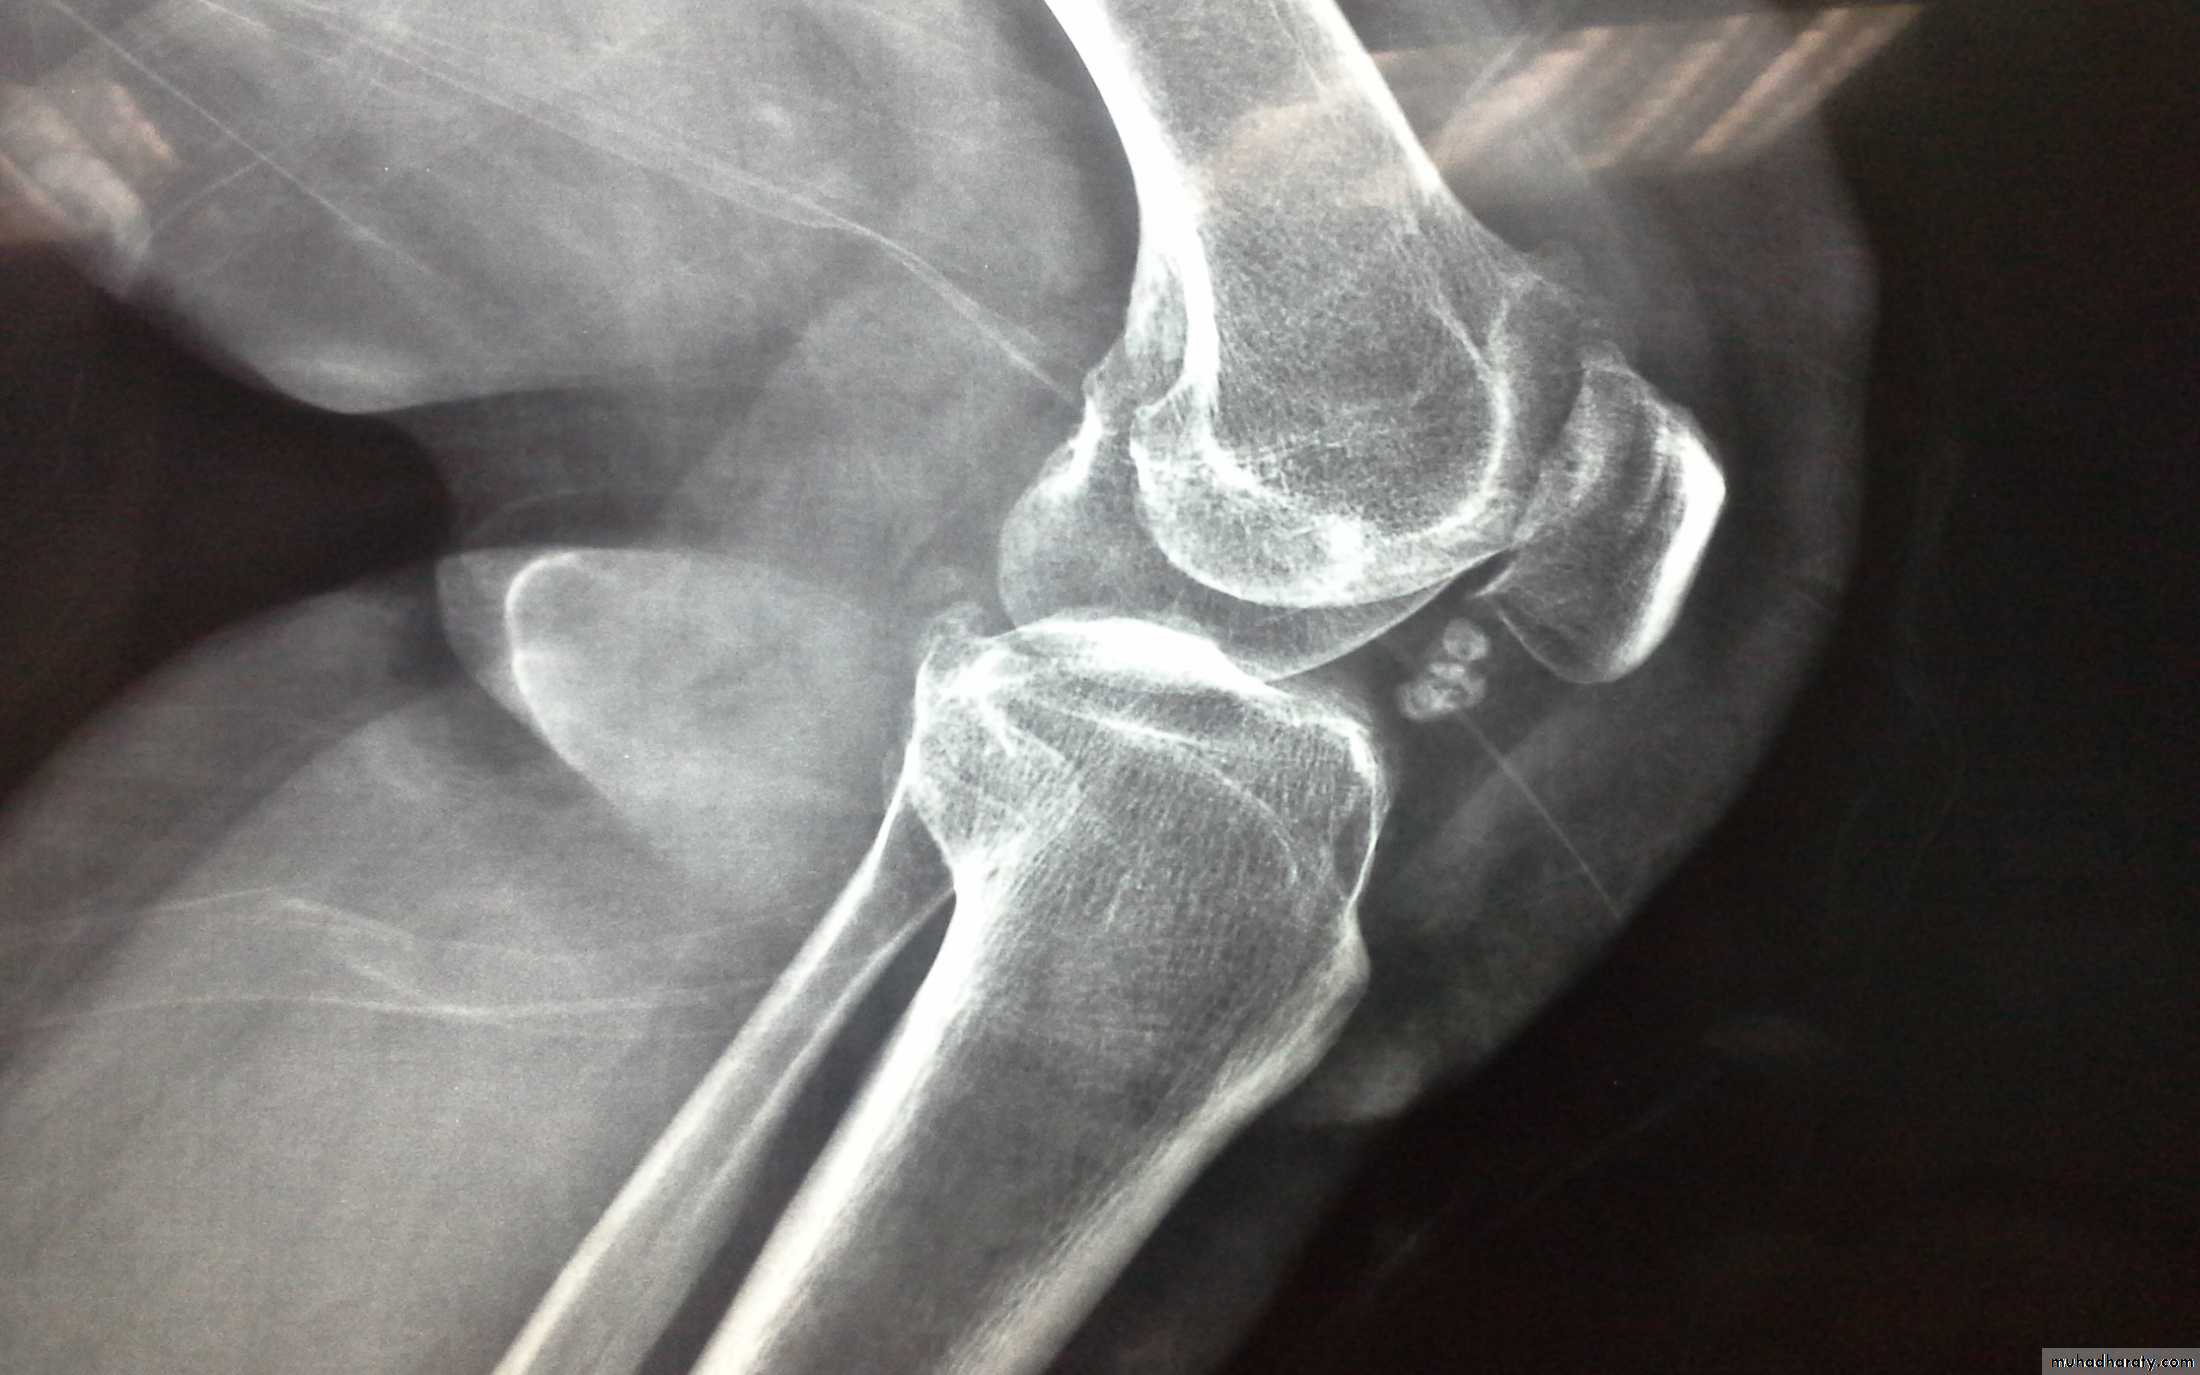

Chronic Pyrophosphate Dihydrate(CPPD)crystal deposition

-CPPD crystal deposition in hyaline and fibro-cartilage of joints( Chondrocalcinosis) is a common age associated phenomenon affects the knee and can cause self limiting synovitis (pseudogout) or chronic arthritis and showing astrong association with nodal OAChronic Pyrophosphate Dihydrate(CPPD)crystal deposition

chondrocalcinosis

2- radiographs: show chondrocalcinosis with or without OA3- secreening for familial or metabolic predisposing factors in patients with :a-early onset disease(under 55 years old)b-polyarticular diseasec-recurrent acute attacksd- clinical or x-ray finding of predisposing disease